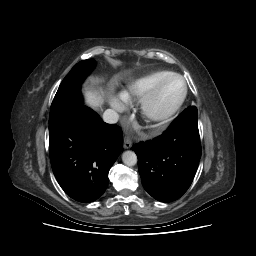

Original VENOUS CT scan

Mediastinum window (WL 40, WW 400 β†’ Low βˆ’160, High +240)

Generated VENOUS CT scan (A→B translation)